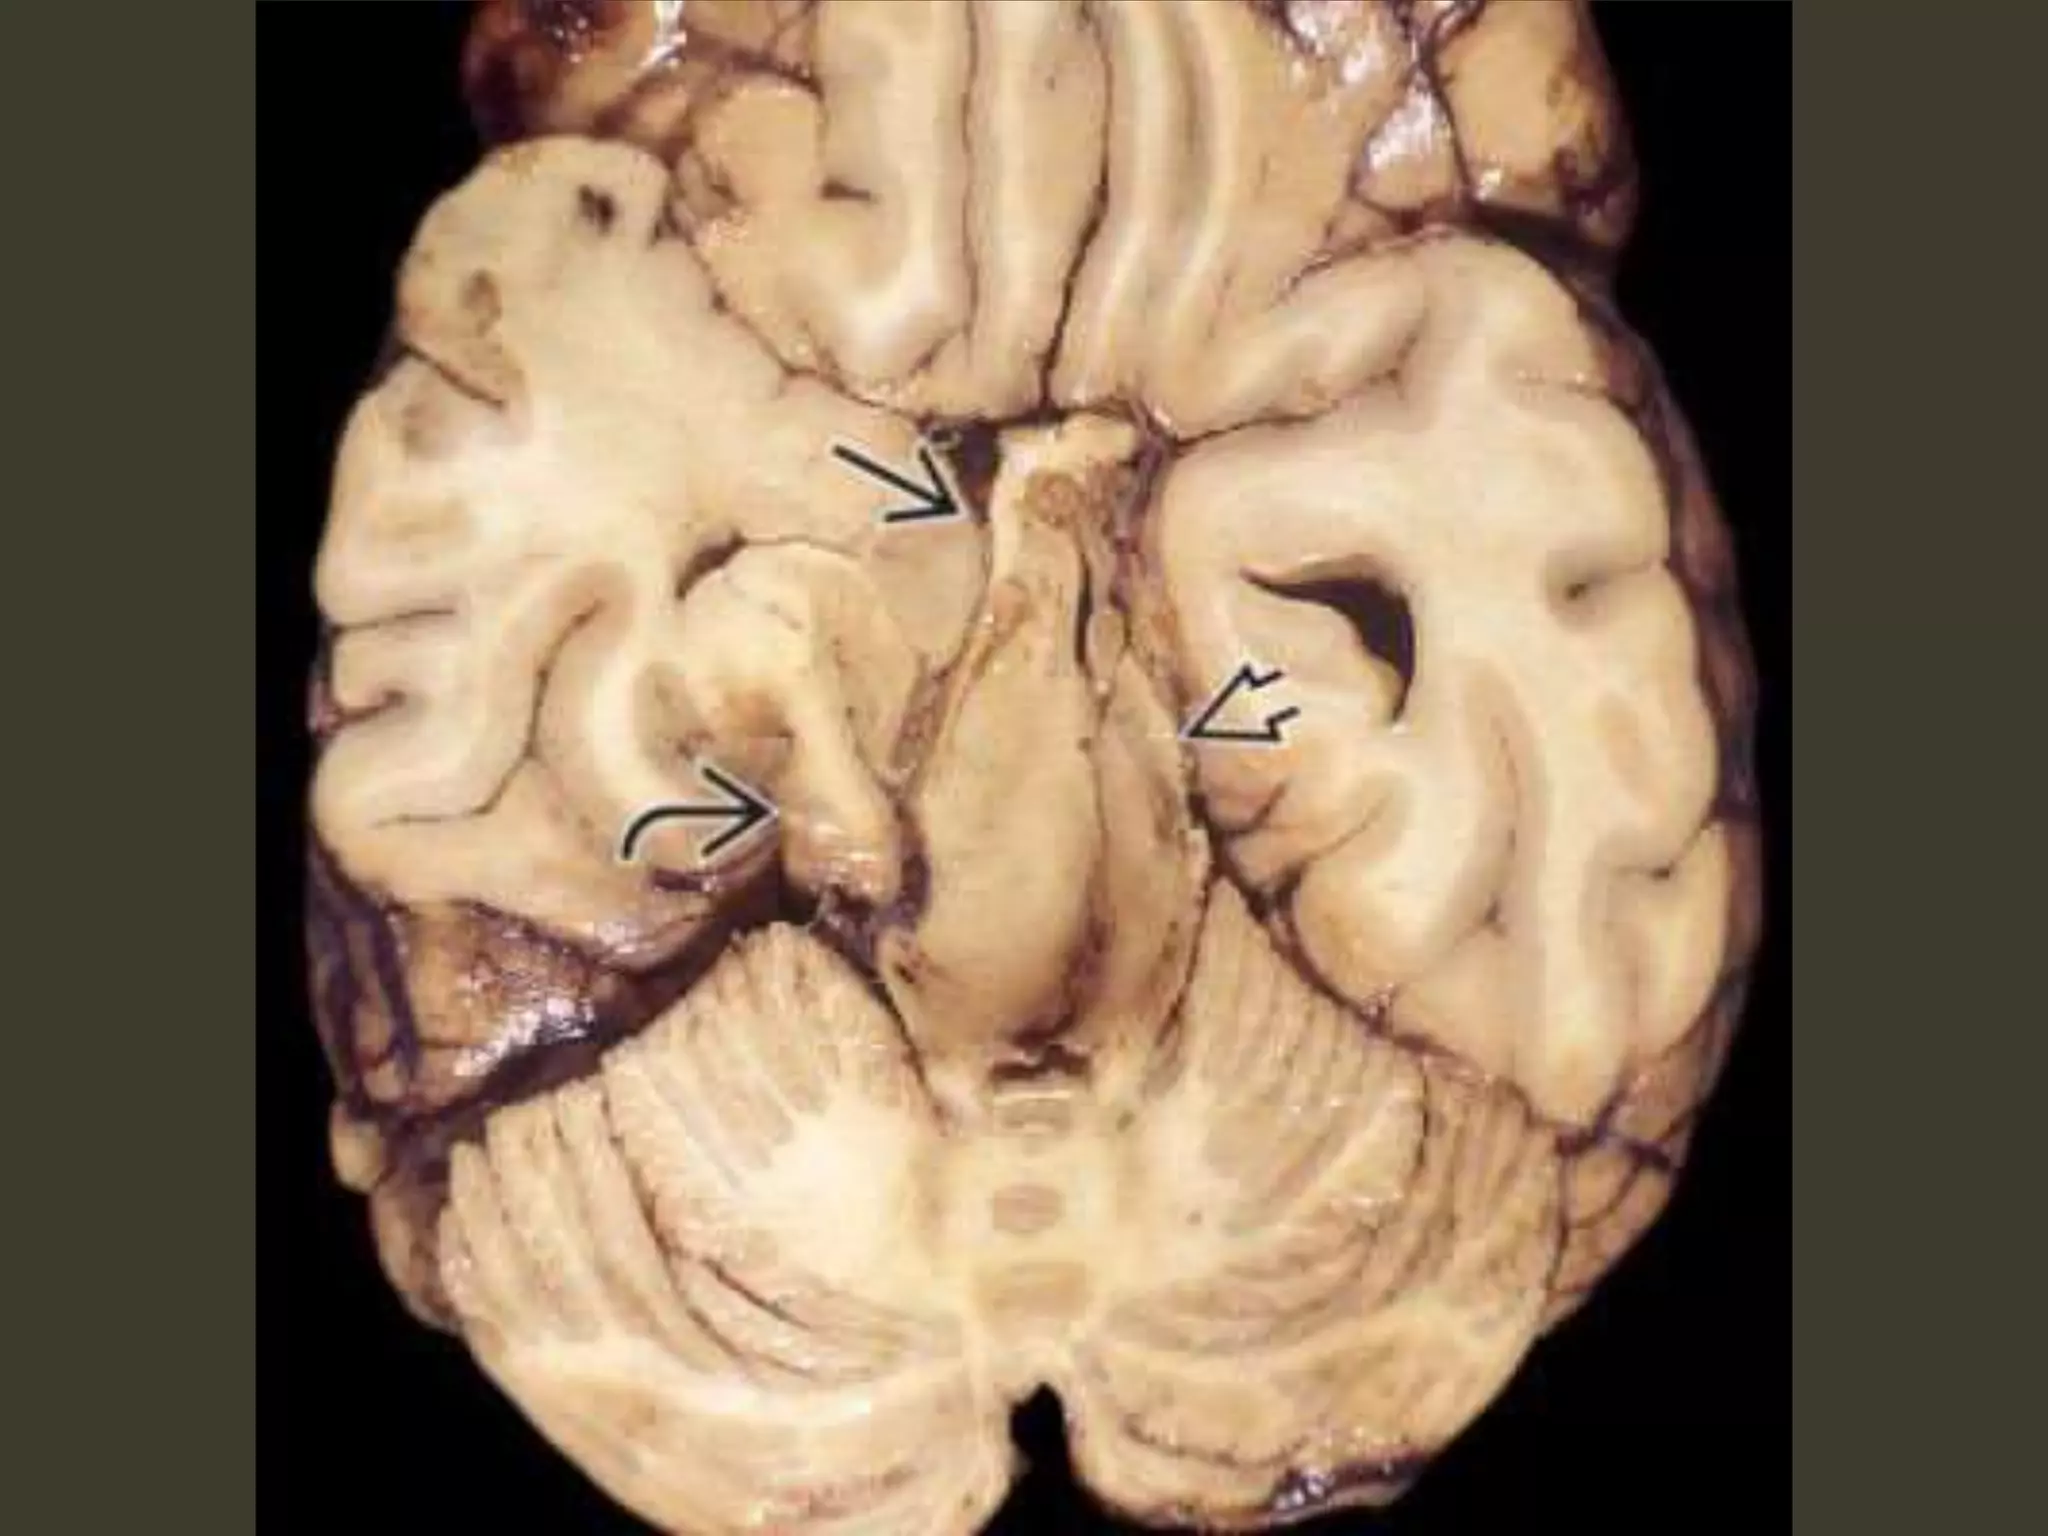

Complications

• CN III (oculomotor) nerve compression

– CN III palsy

• PCA occlusion as it passes back up over the

medial edge of the tentorium

– secondary PCA (occipital) infarct

Kernohan notch

• As the herniating temporal lobe pushes the

midbrain toward the opposite side of the

incisura

– contralateral cerebral peduncle is forced

against the hard edge of the tentorium

• Pressure ischemia 🡪 ipsilateral hemiplegia

– the "false localizing" sign

Duret hemorrhage

"Top-down" mass effect displaces the midbrain

inferiorly

closes the midbrain-pontine angle

Perforating arteries from basilar artery

are compressed and buckled

hypothalamic and basal

ganglia infarcts

complete bilateral DTH

perforating arteries from the

circle of Willis compression against the

central skull base

hypothalamic and basal ganglia

infarcts